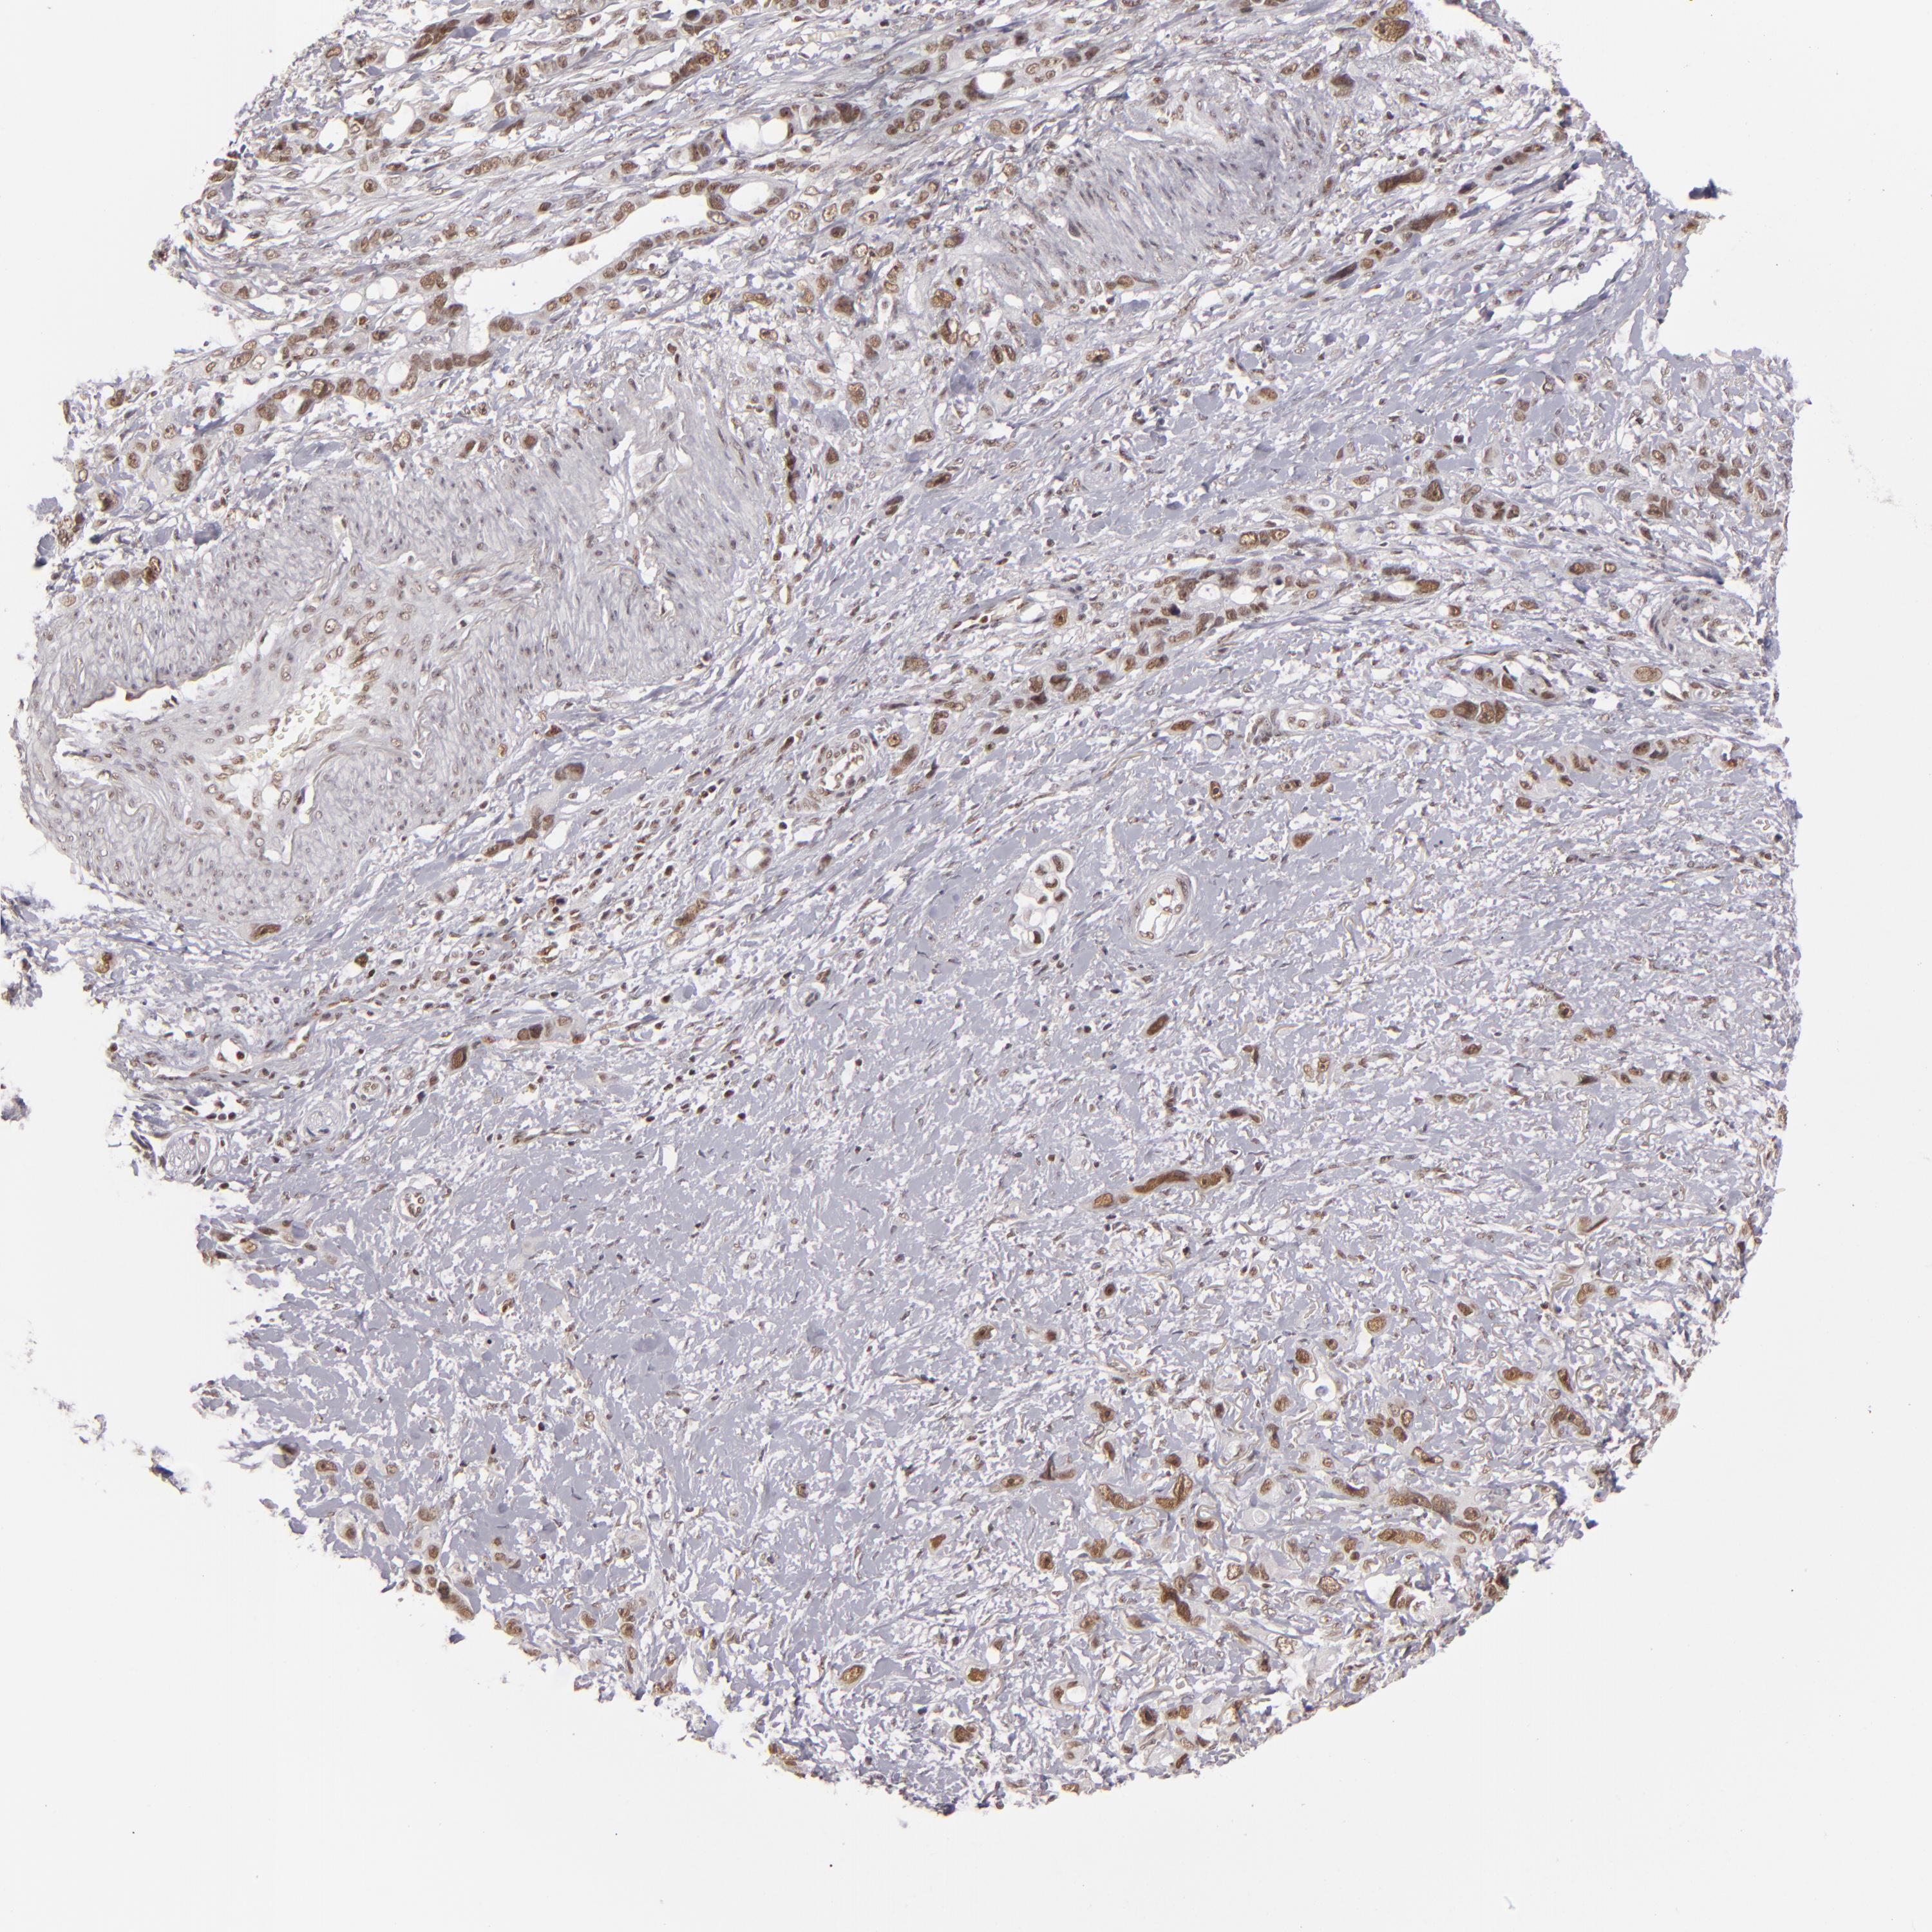

STOMACH CANCER - Protein expressioni

A mouse-over function shows sample information and annotation data. Click on an image to view it in a full screen mode. Samples can be filtered based on level of antibody staining by selecting one or several of the following categories: high, medium, low and not detected. The assay and annotation is described here.

Note that samples used for immunohistochemistry by the Human Protein Atlas do not correspond to samples in the TCGA dataset.

Antibody stainingi

Antibody staining in the annotated cell types in the current human tissue is reported as not detected, low, medium, or high, based on conventional immunohistochemistry profiling in selected tissues. This score is based on the combination of the staining intensity and fraction of stained cells.

Each image is clickable and will lead to virtual microscopy that enables deeper exploration of all samples and also displays staining intensity scores, fraction scores and subcellular localization as well as patient and tissue information for each sample.

Antibody HPA008736

Antibody CAB002224

Antibody CAB025546

Staining

High

Medium

Low

Not detected

Intensity

Strong

Moderate

Weak

Negative

Quantity

>75%

75%-25%

<25%

None

Location

Nuclear

Cytoplasmic/membranous

Cytoplasmic/membranous,nuclear

Adenocarcinoma, NOS

Adenocarcinoma, High grade